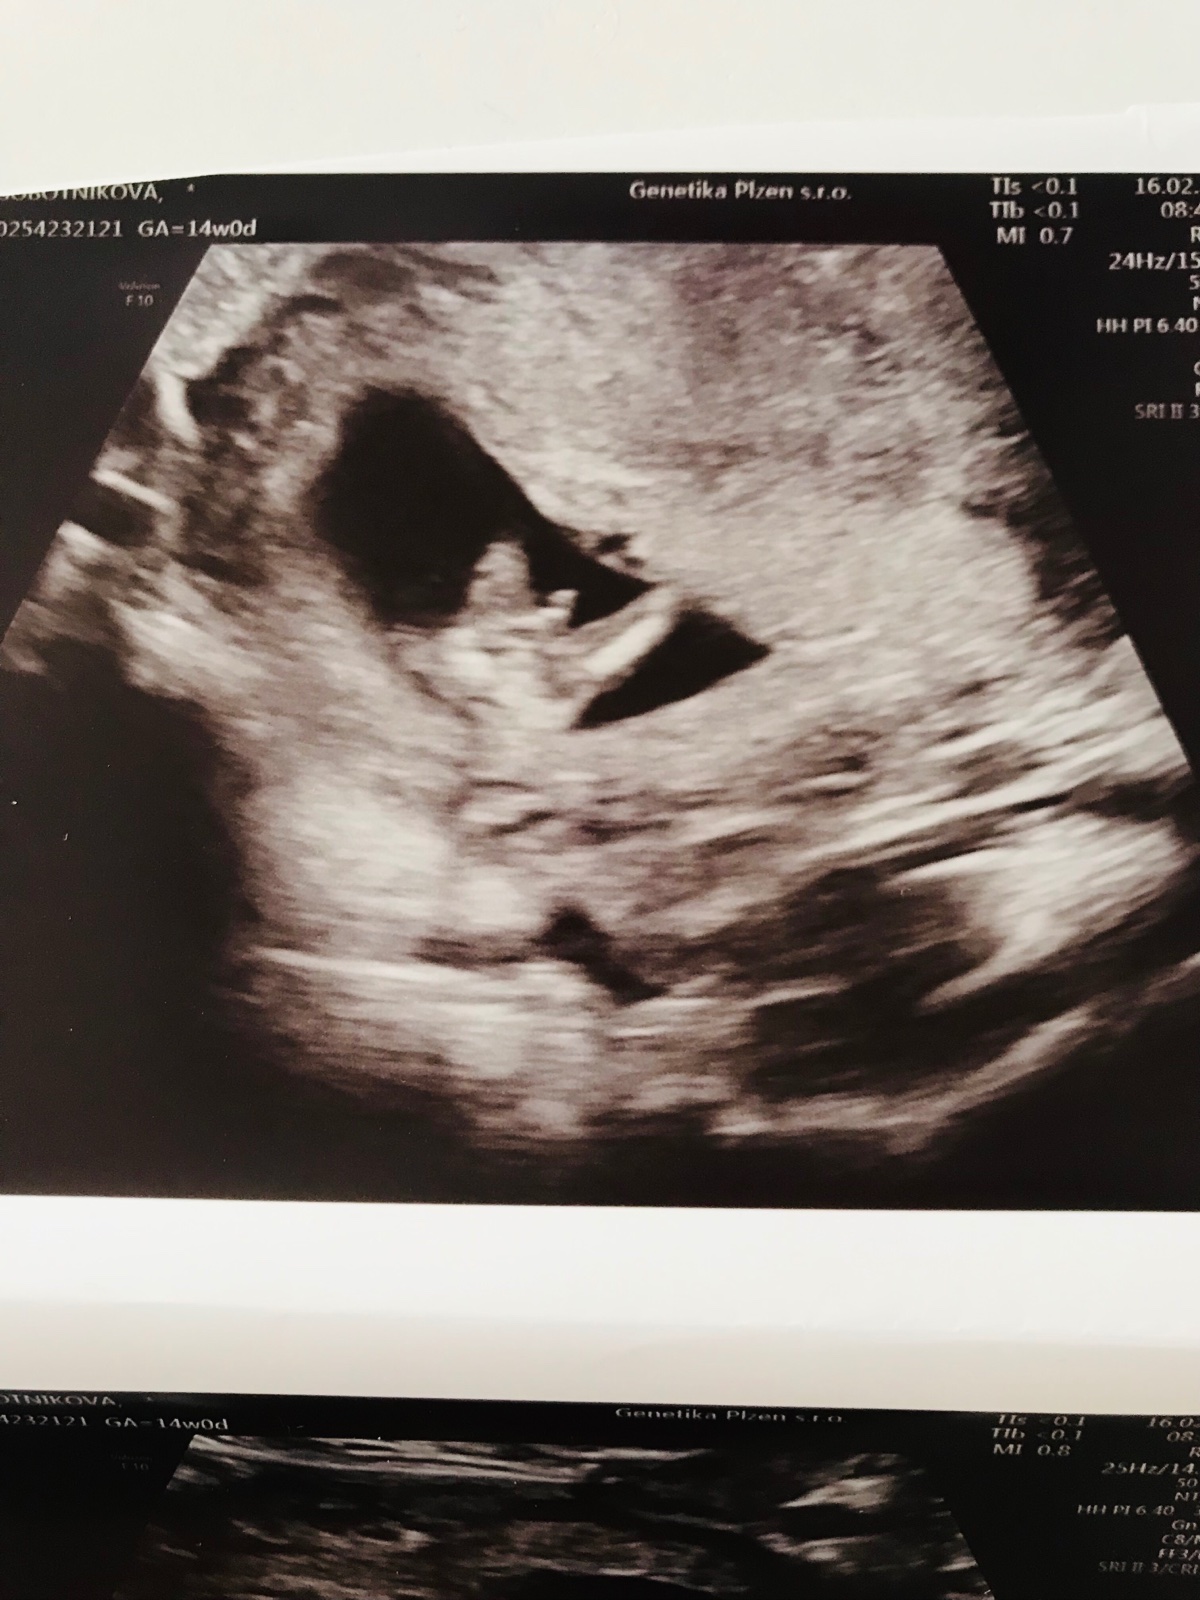

Zdravím dnes jsem byla na screeningu a mám toto foto, doktor řekl ze si myslí, že je to kluk zajímal by mě váš názor myslíte, že je to 🍆?

Příště bych dala fotku ultrazvuku bez rodného čísla. Jinak muze to pít pinďa, ale i pupeční šňůra, určitě bych ještě pockala na další kontrolu, me s jistotou lékařka pohlaví rekla až v 17 tydnu a stejne sem čekala na další potvrzení na druhy screening. 🙂 kolem toho 12-14 se pohlavní orgány teprve zacinaji poradně vyvíjet a zacinaji být rozeznatelné.